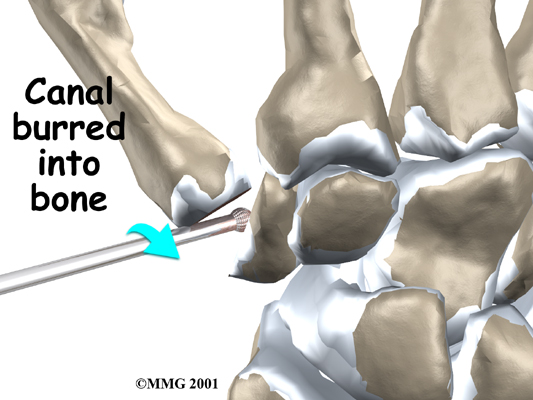

A burr (a small cutting tool) is used to make a canal into the bones that form the thumb joint. The surgeon sizes the stem of the prosthesis to ensure a snug fit into the canal and inserts it. When the new joint is in place, the surgeon wraps the joint with a strip of nearby tendon. This gives the new implant some added protection and stability.

A burr is used to make a small notch, or canal, in the ends of the two bones. The surgeon shapes the notch so the ball-shaped implant will fit snugly in the joint. The implant is placed between the ends of the shaped bones.

View animation of of canal formation